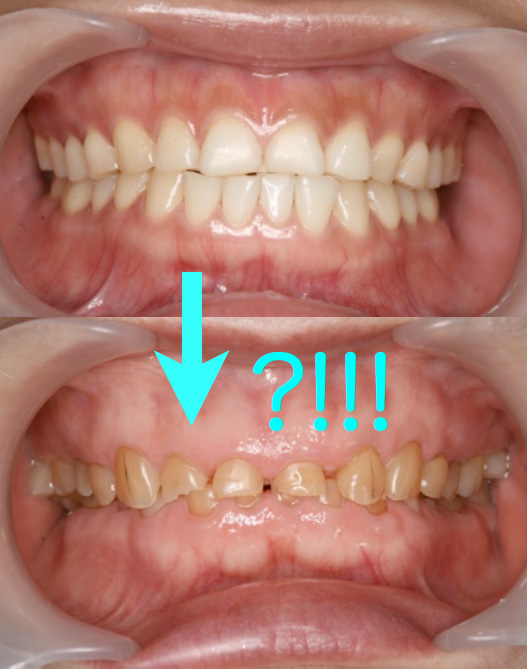

をしています。前歯が歯ぎしりで短くなっているけど・・。し

かし、「矯正」すればすべてOKなんでしょうか?その前にホ

ントに矯正すれば彼女の主訴は治るんでしょうか???やって

みてダメなら「ああ、治らなかったね。」って2年後に言われ

るんですか?本来楽しく輝くはずの20代のうちの2年間を矯正

装置を付けて過ごして、それが無駄になる?ありえないで

しょ。